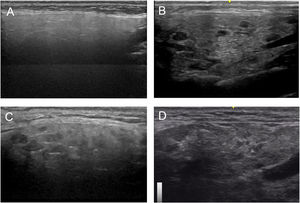

Based on all of the possible glandular aspects assessed with US (hyperechoic lines, number and size of hypoechoic images, etc.), we evaluated only parenchymal homogeneity for diagnostic purposes in accordance with the available literature.10 These findings were graded based in the experience of the authors with a 4 grades semiquantitative score, quite similar to the proposed by OMERACT group in 20192 that considers parenchymal homogeneity ranging from 0 to 3 and can be assessed in both parotid (Fig. 1) and submandibular (Fig. 2) glands. The definition of each grade is specified below: Grade 0: homogeneous normal glandular parenchyma; grade I: minimal glandular heterogeneity without hypoechoic images; grade II: moderate parenchymal heterogeneity with hypoechoic images; grade III: severe heterogeneity with hypoechoic lesions in the entire glandular parenchyma.